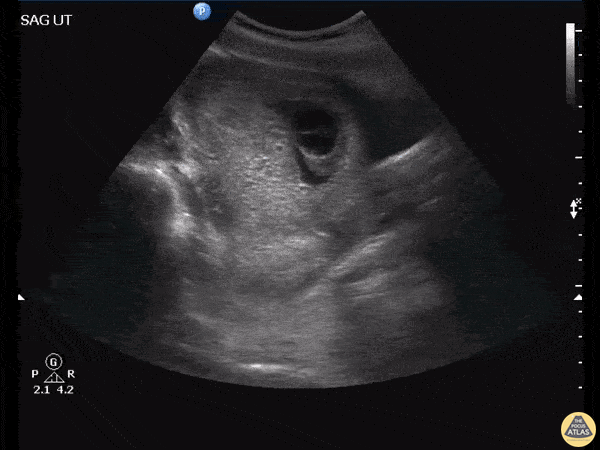

This is a saggital view of the uterus belonging to a patient who returned to the emergency department after persistent vomiting. An initial urine pregnancy test performed yielded a negative result however this patient’s ultrasound scan ultimately revealed a molar pregnancy. As Dr. Jones explains, this patient false-negative urine pregnancy test is explained by a phenomenon known as the High Dose Hook Effect. Image courtesy of Robert Jones DO, FACEP @RJonesSonoEM Director, Emergency Ultrasound; MetroHealth Medical Center; Professor, Case Western Reserve Medical School, Cleveland, OH View his original post here